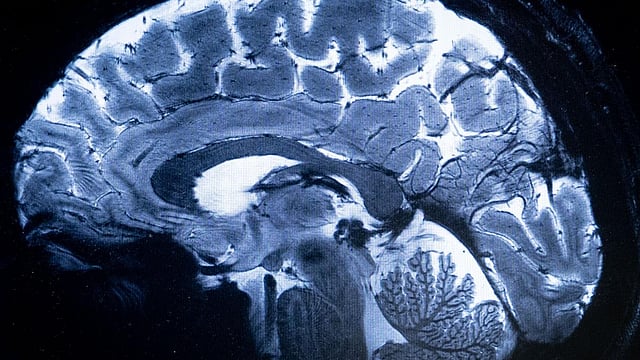

amoebic meningoencephalitis is a rare brain infection caused by Naegleria fowleri

KOZHIKODE: The health department has issued additional cautionary instructions post the death of a girl due to amoebic meningoencephalitis in Thamarassery. Nine-year-old Anaya Sanoop died of primary amoebic meningoencephalitis on Thursday. The health department has instructed people to refrain from bathing in ponds, water bodies, streams, rivers etc. within the limits of Thamarassery panchayat.